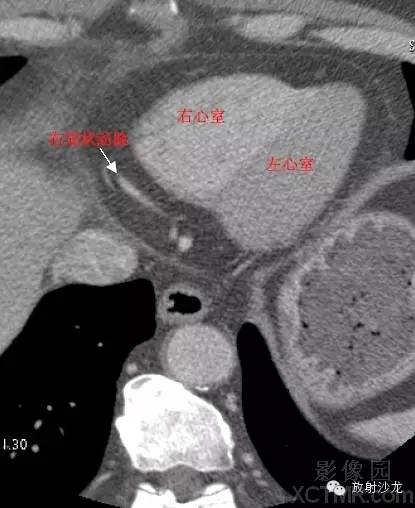

LV -Left Ventricle左心室

RV -Right Ventricle右心室

RCA -Right Coronary Artery 右冠状动脉